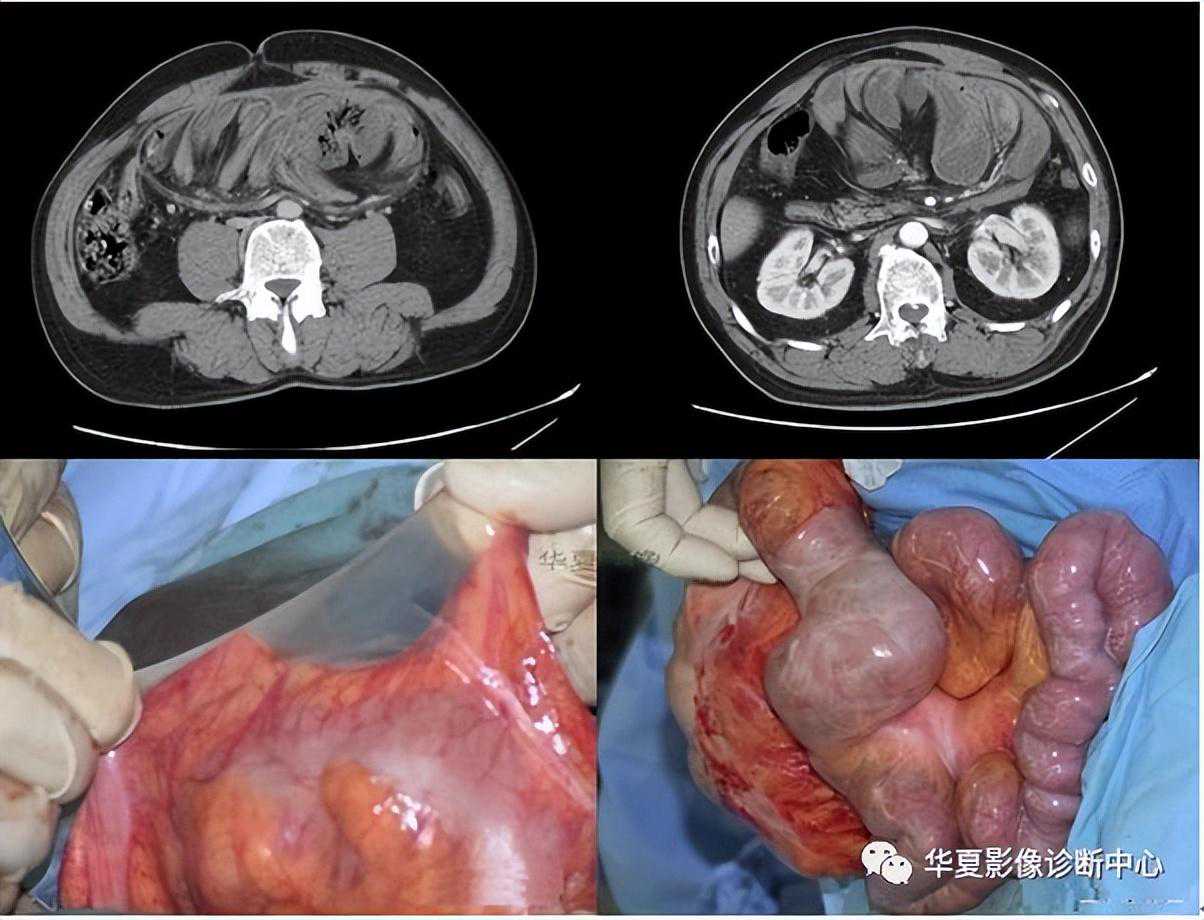

027:腹茧症:全部或部分小肠被一层致密、灰白色的纤维膜所包裹,形似“蚕茧”,故称为腹茧症,又称为特发性硬化性腹膜炎、小肠禁锢症、小肠纤维膜包裹症等。多见于青春期女性。腹部CT十二指肠空肠交界处扭曲,肠系膜增厚伴上消化道扩张,提示不全性肠梗阻。X线可发现全部或部分小肠聚拢于某一部分,位置固定。CT检查有更助于腹茧症的术前诊断。CT能显示梗阻程度及包块内肠管的情况,还能显示包裹在肠管周围的纤维包膜。一旦观察到包膜便可诊断腹茧症。典型的CT表现为扩张的小肠肠袢固定在腹部的某一部位,并被增厚的包膜所包裹或分割。增强扫描示包膜强化明显,部分病例可见腹腔积液及肠管间积液。